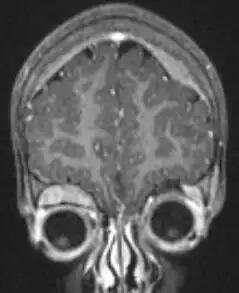

MRI showing orbital and skull vault metastatic NB in 2-year-old

The diagnosis is usually confirmed by a surgical pathologist, taking into account the clinical presentation, microscopic findings, and other laboratory tests. It may arise from any neural crest element of the sympathetic nervous system (SNS).